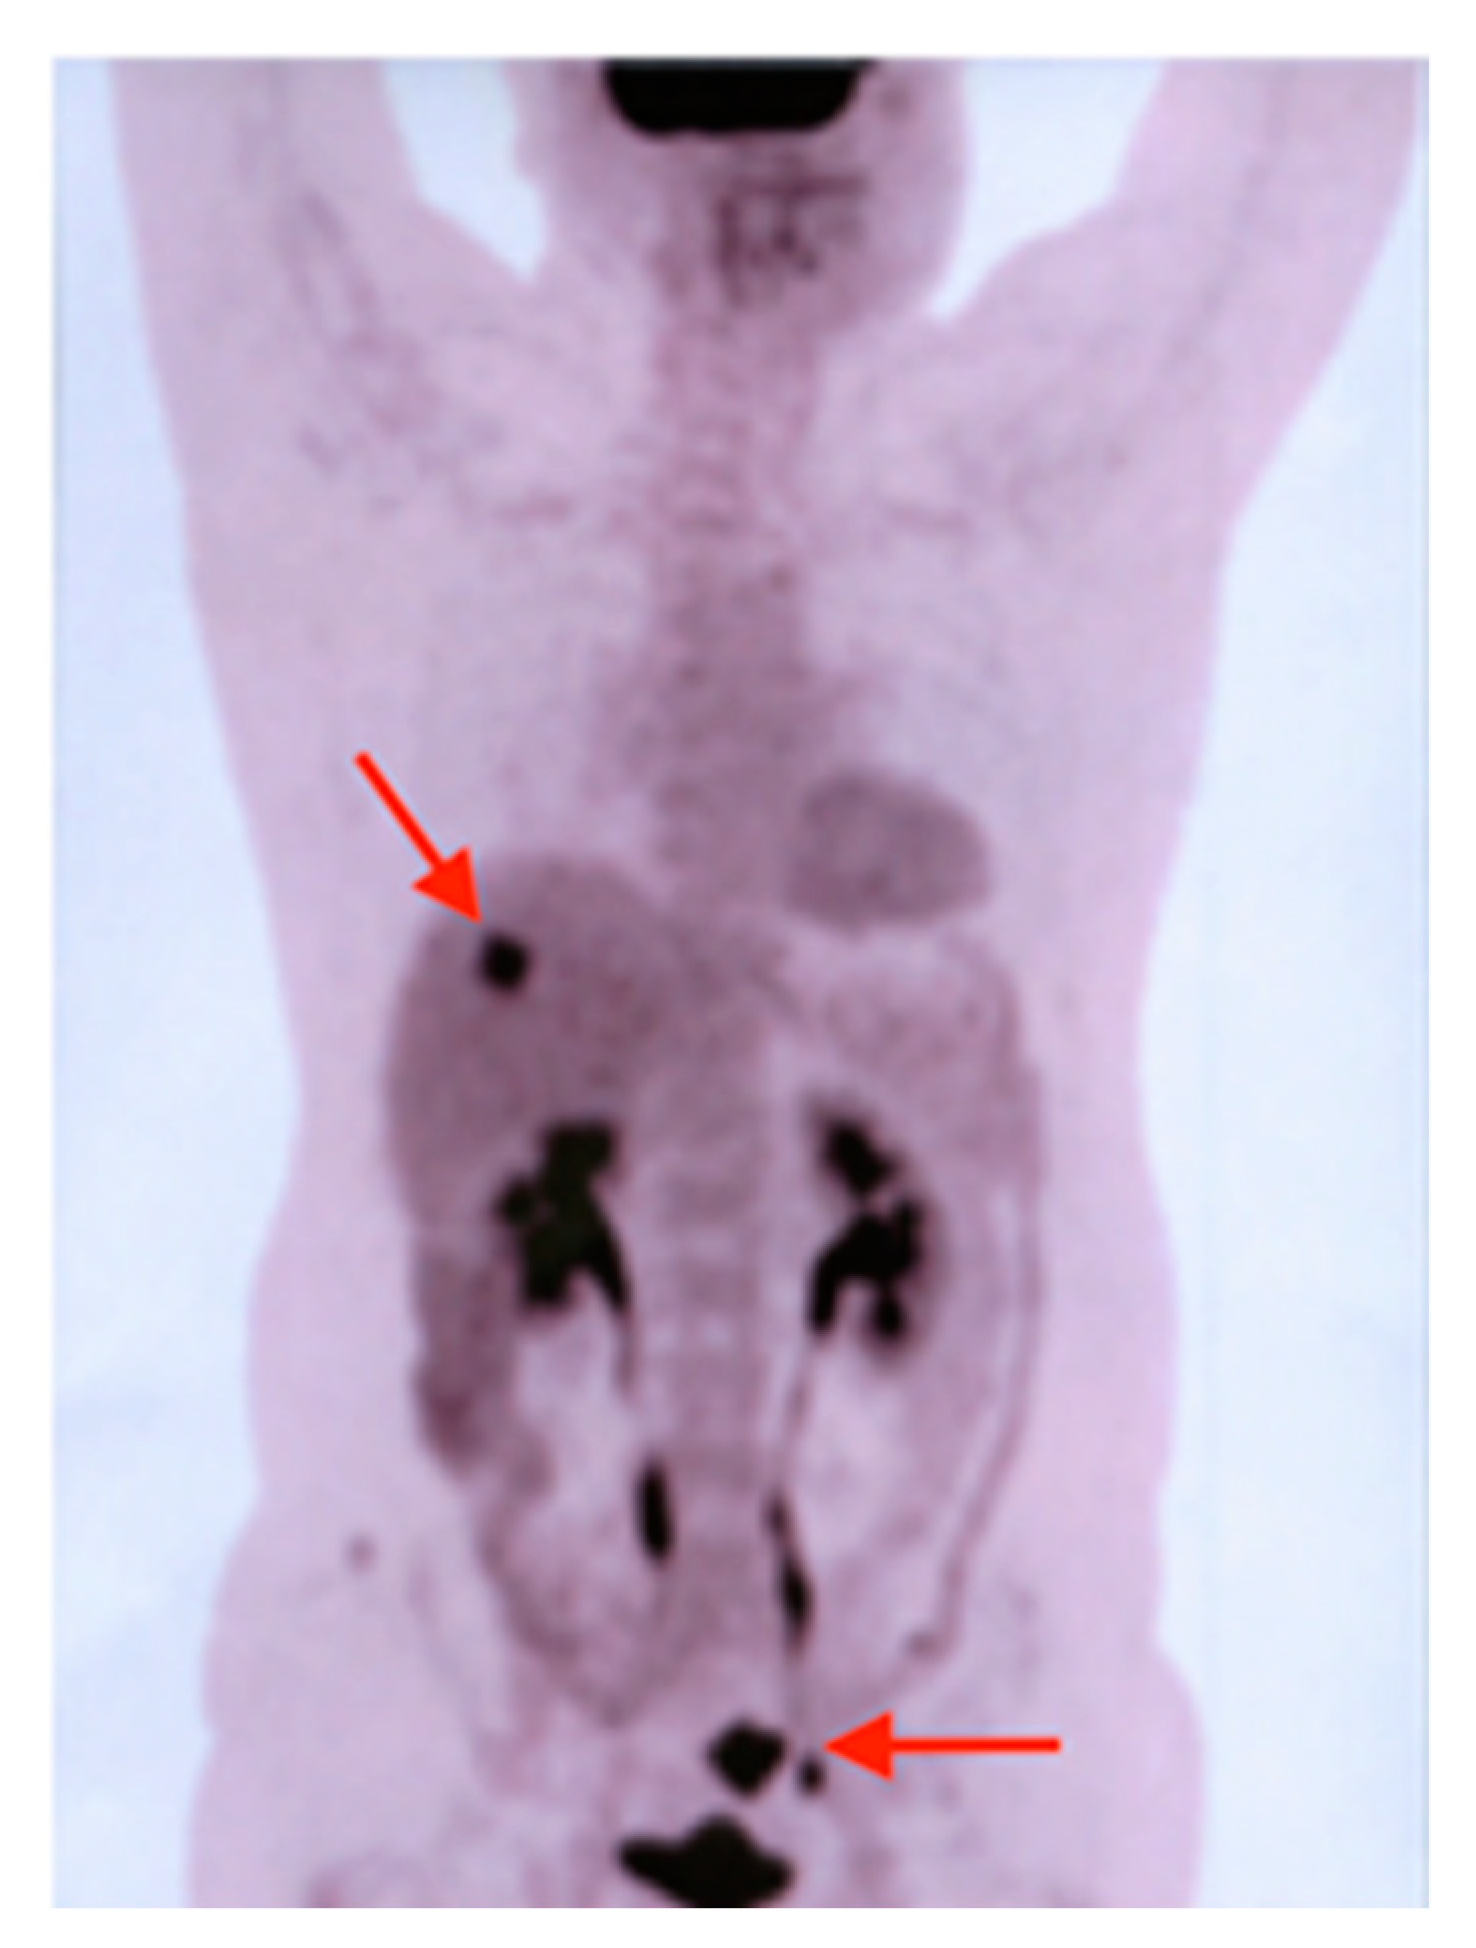

In 2007, an F18-FDG PET-CT scan was performed, which revealed a 30/28 mm focal increase of uptake in the sigmoid colon and a lesion of 21 mm in the VIIth liver segment, consisting of a colon malignant tumor with liver metastases (Figure 6). The patient was submitted for hemicolectomy and liver metastases resection, followed by chemotherapy. In 2013, during the routine examination, we found a focal uptake in the right prostatic lobe. After the prostatectomy, the histopathological result showed a prostate adenocarcinoma, occurring in a patient with already known thyroid and colon carcinomas (Figure 7).

Figure 6. MIP image of F18-FDG PET-CT revealing a lesion in the sigmoid colon (lower-right red arrow) and a lesion of 21 mm in the VIIth liver segment (upper-left red arrow), consisting of a colon malignant tumor with liver metastases.